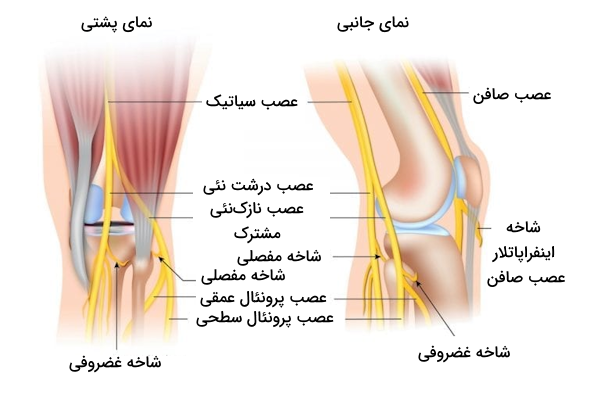

عصبرسانی به زانو

«عصب رانی» (Femoral Nerve) مسئول عصبرسانی به مفصل زانو است، این فرآیند از طریق «عصب صافن» (Saphenous Nerve) و شاخههای ماهیچهای انجام میشود. این مفصل از اعصابی که در ادامه نام میبریم نیز عصب دریافت میکند.

- «عصب نازکنئی مشترک» (Common Peroneal Nerves)

- «عصب درشت نئی» (Tibial Nerves)

- شاخه پشتی «عصب سدادی» (Obturator Nerve)